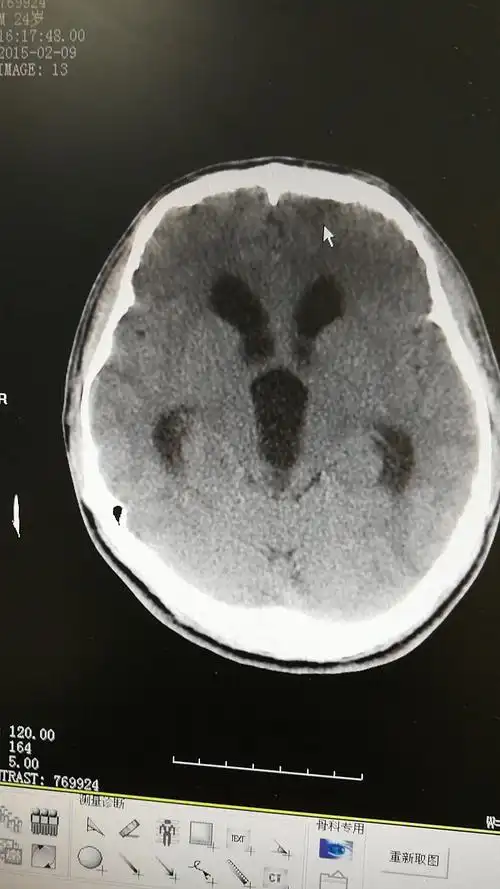

手术后可以明显改善症状,效果明显.脑积水ct显示:侧脑室,三脑室扩大